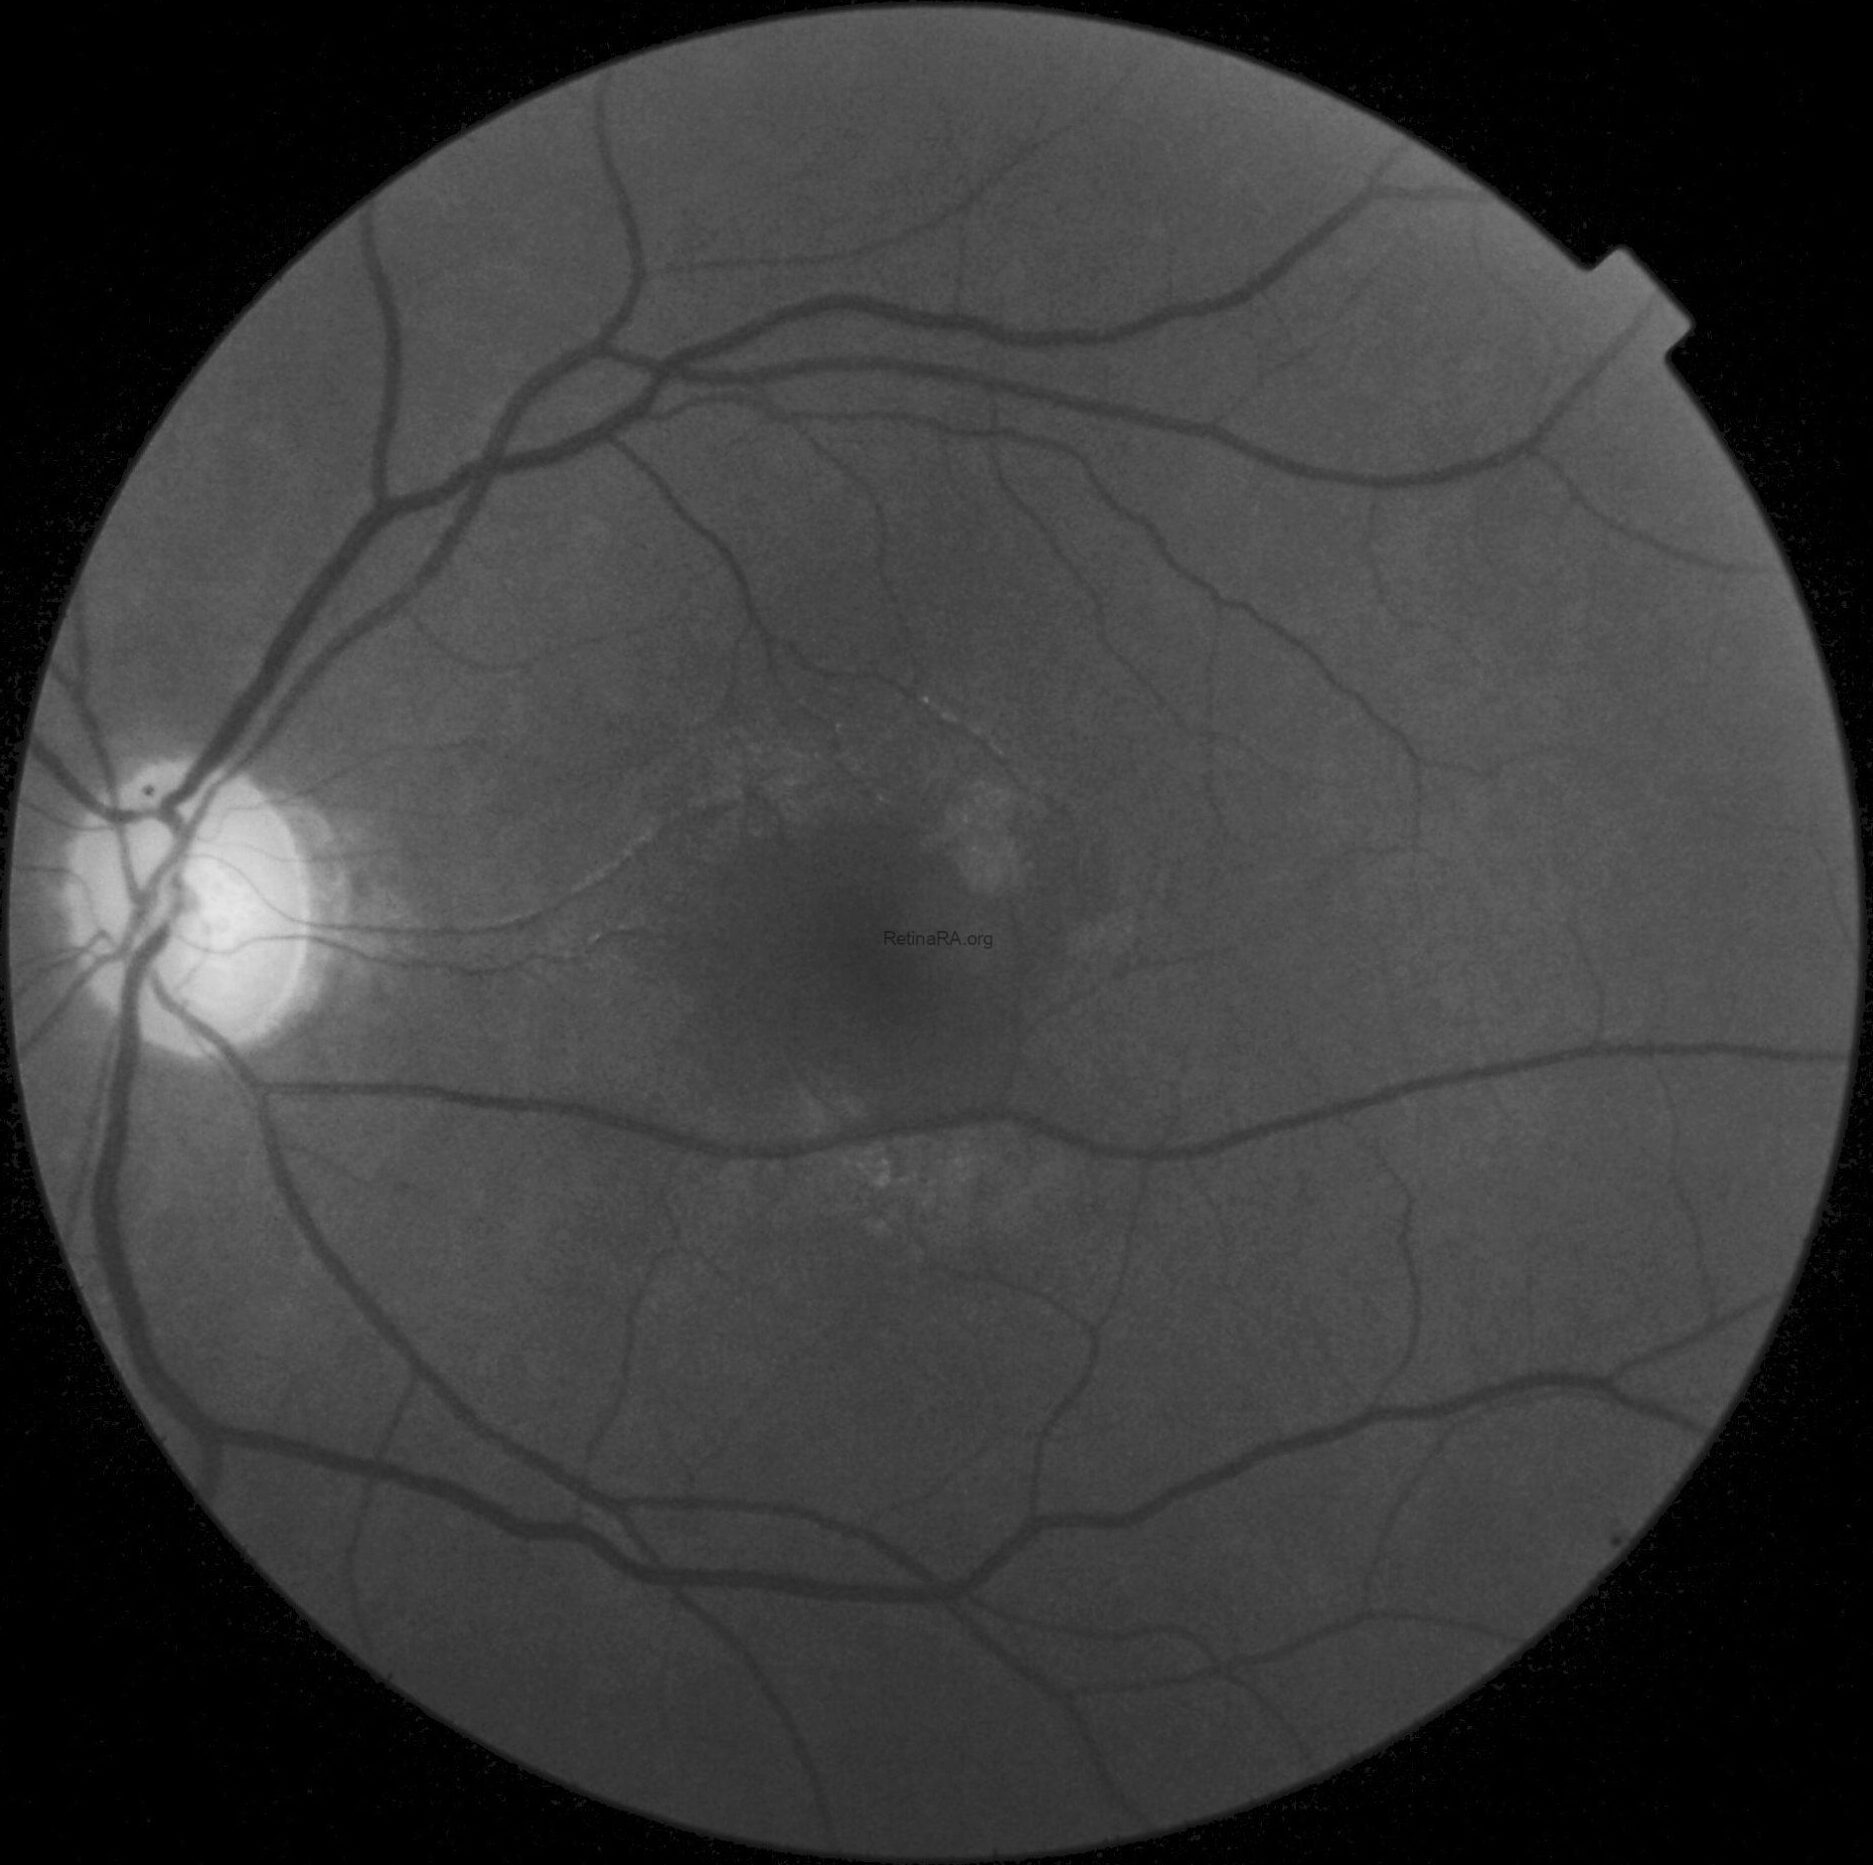

Color fundus photography in OD revealed mild RPE dystrophy in the nasal macular region and a crescent zone of temporal peripapillary chorioretinal atrophy consistent with glaucomatous beta-zone.

CFP in OS, however, showed marked optic nerve pallor associated with glaucomatous beta-zone temporal peripapillary atrophy, baring of circumlinear blood vessels and an extensive anomalous macular reflex, starting from the temporal edge of the optic disc and proceeding up to the perifoveal region, ultimately extending around the fovea itself.

These findings are better highlighted with red-free photography, which demonstrates a full encircling of the fovea by the anomalous reflex and furthermore displays extensive RNFL defects in the left eye when compared to the right eye.